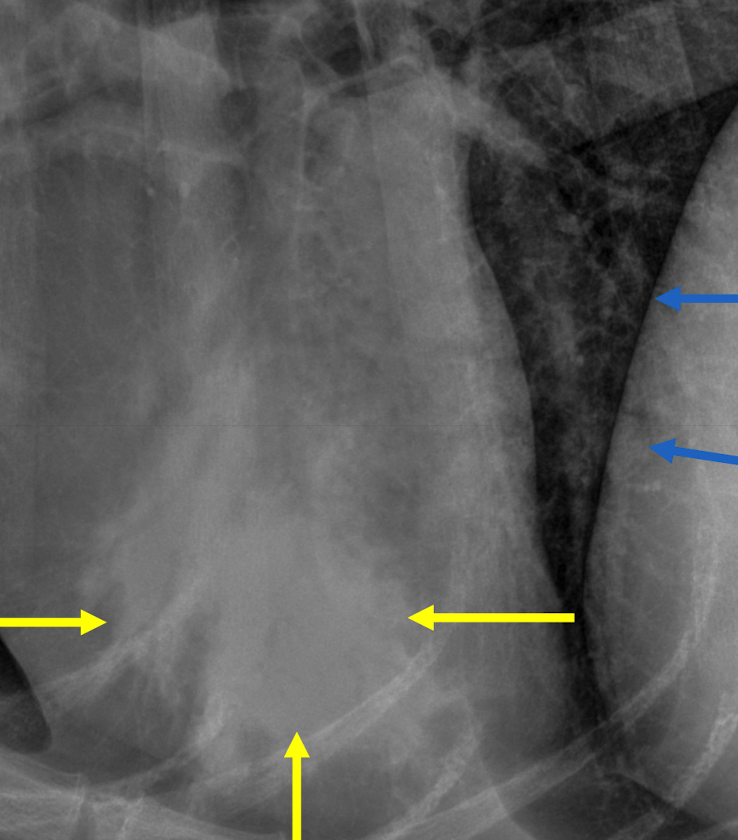

signs of pneumothorax on xray

lung lobe margin retraction radiolucent pleual space with no pulmonary vessels cardiac silhouette seperated from sternum by gas

pneumothorax Lung lobe margin retraction Radiolucent pleural space – Devoid of pulmonary vessels

**pneumothorax** Lung lobe margin retraction Radiolucent pleural space – Devoid of pulmonary vessels **Cardiac silhouette separated from sternum by air**

pneumo?

no - just normal deep chested dog- can see vessels in space below heart if you zoom